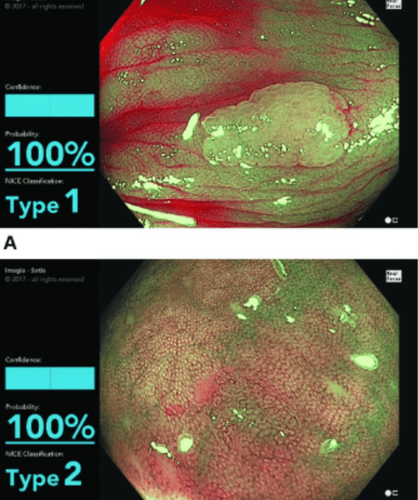

Trí tuệ nhân tạo (AI) đã được ứng dụng trong lĩnh vực y tế từ đầu những năm 1950. AI được định nghĩa là bất kỳ máy nào có chức năng nhận thức bắt chước con người, ví dụ như giải quyết vấn đề hoặc học tập. Mô hình học máy, là một loại phụ của AI, được đặc trưng bởi một tập hợp các phương pháp có thể tự động phát hiện các mẫu trong dữ liệu và sau đó sử dụng các mẫu chưa được phát hiện để dự đoán kết quả. Các hệ thống AI thông thường sử dụng một loại mô hình học máy được giám sát để trích xuất các hiệp biến của dữ liệu đào tạo để đạt được nhận dạng hoặc phân loại mẫu. Điều quan trọng cần lưu ý là mỗi phần thông tin được đưa vào biểu diễn của bệnh nhân được gọi là hiệp biến, và loại máy học truyền thống, ví dụ:., hồi quy logistic, chỉ kiểm tra các mối quan hệ của "biến cố xác định trước" với kết quả. Tuy nhiên, mô hình học máy không thể thay đổi cách xác định các hiệp biến. Mô hình học sâu thực sự giải quyết vấn đề này bằng cách xác định các hiệp biến và xây dựng các khái niệm phức tạp từ các hiệp biến đơn giản, đặc biệt hữu ích trong việc phân loại hình ảnh và vị trí đối tượng vì các đặc điểm của một nhóm các đối tượng tương tự có thể phức tạp và khó xác định bởi con người (Hình 1).

Trong những năm gần đây, mô hình học sâu ngày càng được sử dụng nhiều hơn trong việc phát hiện và xác định vị trí của các polyp đại trực tràng. Sau khi dữ liệu đào tạo được cung cấp với nhãn thích hợp, mô hình học sâu có thể tự động trích xuất các tính năng quan trọng trong dữ liệu đào tạo để phân biệt và phân loại. Không cần sự can thiệp hoặc chỉ dẫn của con người, các thông số bên trong của mỗi "nơ-ron" trong một lớp đơn lẻ sẽ được điều chỉnh theo hướng mô hình có mức độ sai sót ít nhất. Kiến trúc phổ biến nhất được sử dụng trong mô hình học sâu của các nghiên cứu nội soi đại tràng ban đầu là mạng nơ-ron phức tạp, mô phỏng cấu trúc của não người và chứa nhiều lớp với "tế bào thần kinh nhân tạo" dưới mỗi lớp. Các lớp phức tạp thực sự hoạt động như một bộ lọc để trích xuất các tính năng quan trọng từ hình ảnh hoặc dữ liệu gốc. Các lớp gộp có thể giảm kích thước các tham số của các lớp để hợp lý hóa việc tính toán bên dưới. Cuối cùng, với các lớp được kết nối đầy đủ, các tính năng này được kết hợp với nhau để tạo ra một mô hình để phân loại các đầu ra khác nhau.

Phân tích tổng hợp của các tác giả về các nghiên cứu AI được công bố gần đây về phát hiện polyp đại trực tràng cho thấy rằng một hệ thống AI được thiết kế tốt có thể đạt được độ chính xác hơn 90%. So với thuật toán dựa trên máy học truyền thống, các nghiên cứu sử dụng mô hình học sâu được phát hiện có độ chính xác cao (lên đến 91%) với độ nhạy tổng hợp là 94% và độ đặc hiệu là 92% khi phát hiện polyp đại trực tràng.